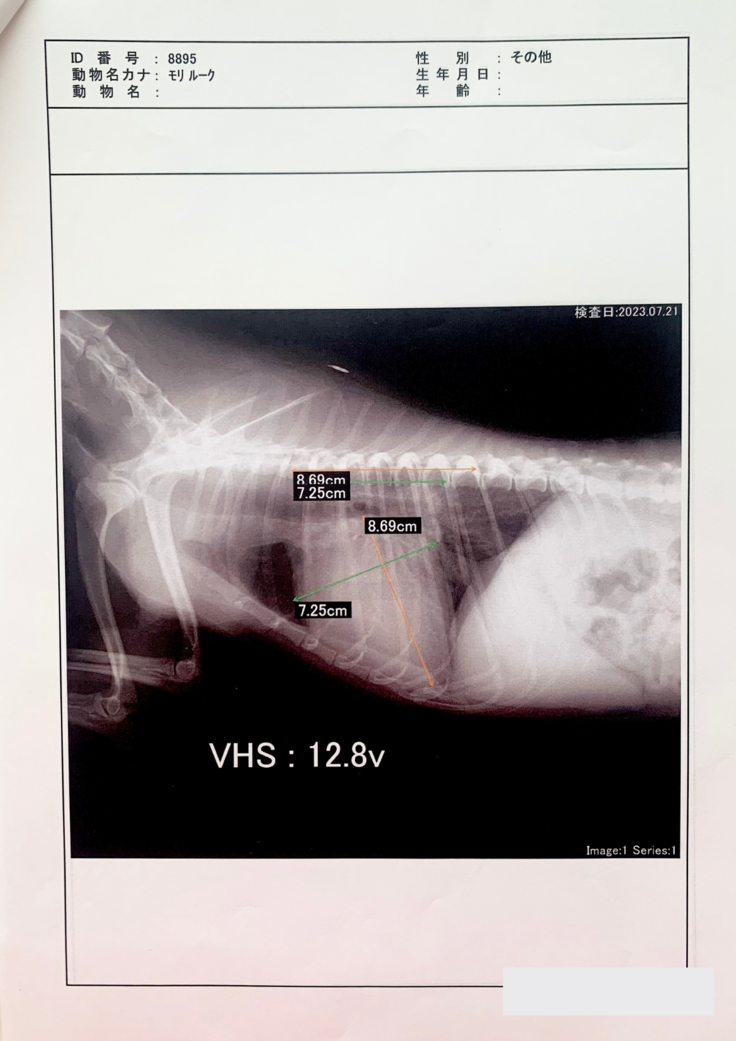

度々の咳が続き、気になり検査したところ、2023年の1月に、「僧帽弁閉鎖不全症」という病気だったということが分かりました。

僧帽弁とは、左側の左心房と左心室の間にある弁のことです。通僧帽弁の働きにより左心房から左心室への一方向にしか血液は流れませんが、僧帽弁閉鎖不全症では、弁がうまく閉まらなくなることで逆方向の血流が認められるようになります。心臓が大きくなると、心臓だけでなく肺にも血液が溜まり、肺水腫と呼ばれる状態になります。

手術でしか治るものはなく、それをしなければ薬で延命治療をするというものです。

その後2月、4月、7月に病院に行っています。

最終的に肺水腫と気管虚脱も発症しており、

かなりの重症でした。